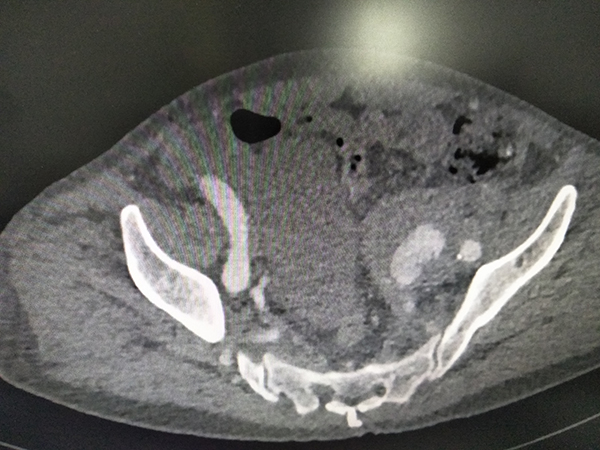

72岁的何先生,因下腹部疼痛3天急诊入院,经腹部CTA检查,被诊断为腹主动脉夹层动脉瘤、双侧髂总动脉瘤先兆破裂、左侧髂内动脉瘤破裂,病情极其危重,随时都可能有生命危险。

CT检查 10月23日,在华西医院黄斌副教授的现场指导下,胸心血管外科、放射科科、介入导管室等多科室医护人员的通力配合下,在局麻下完成经双侧股动脉腹主动脉瘤、双侧髂总动脉瘤、左侧髂内动脉瘤腔内覆膜支架修复术+左侧髂内动脉瘤、右侧髂内动脉弹簧圈栓塞术+球囊扩张术,手术过程顺利,患者获得成功救治。术后当日患者恢复饮食,第二天下床活动,1周后康复出院。